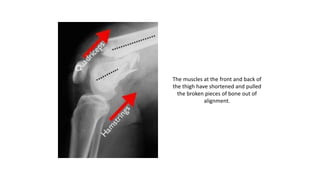

• When the distal femur breaks, both the hamstrings and quadriceps

muscles tend to contract and shorten. When this happens the bone

fragments change position and become difficult to line up with a cast.

The muscles at the front and back of

the thigh have shortened and pulled

the broken pieces of bone out of

alignment.